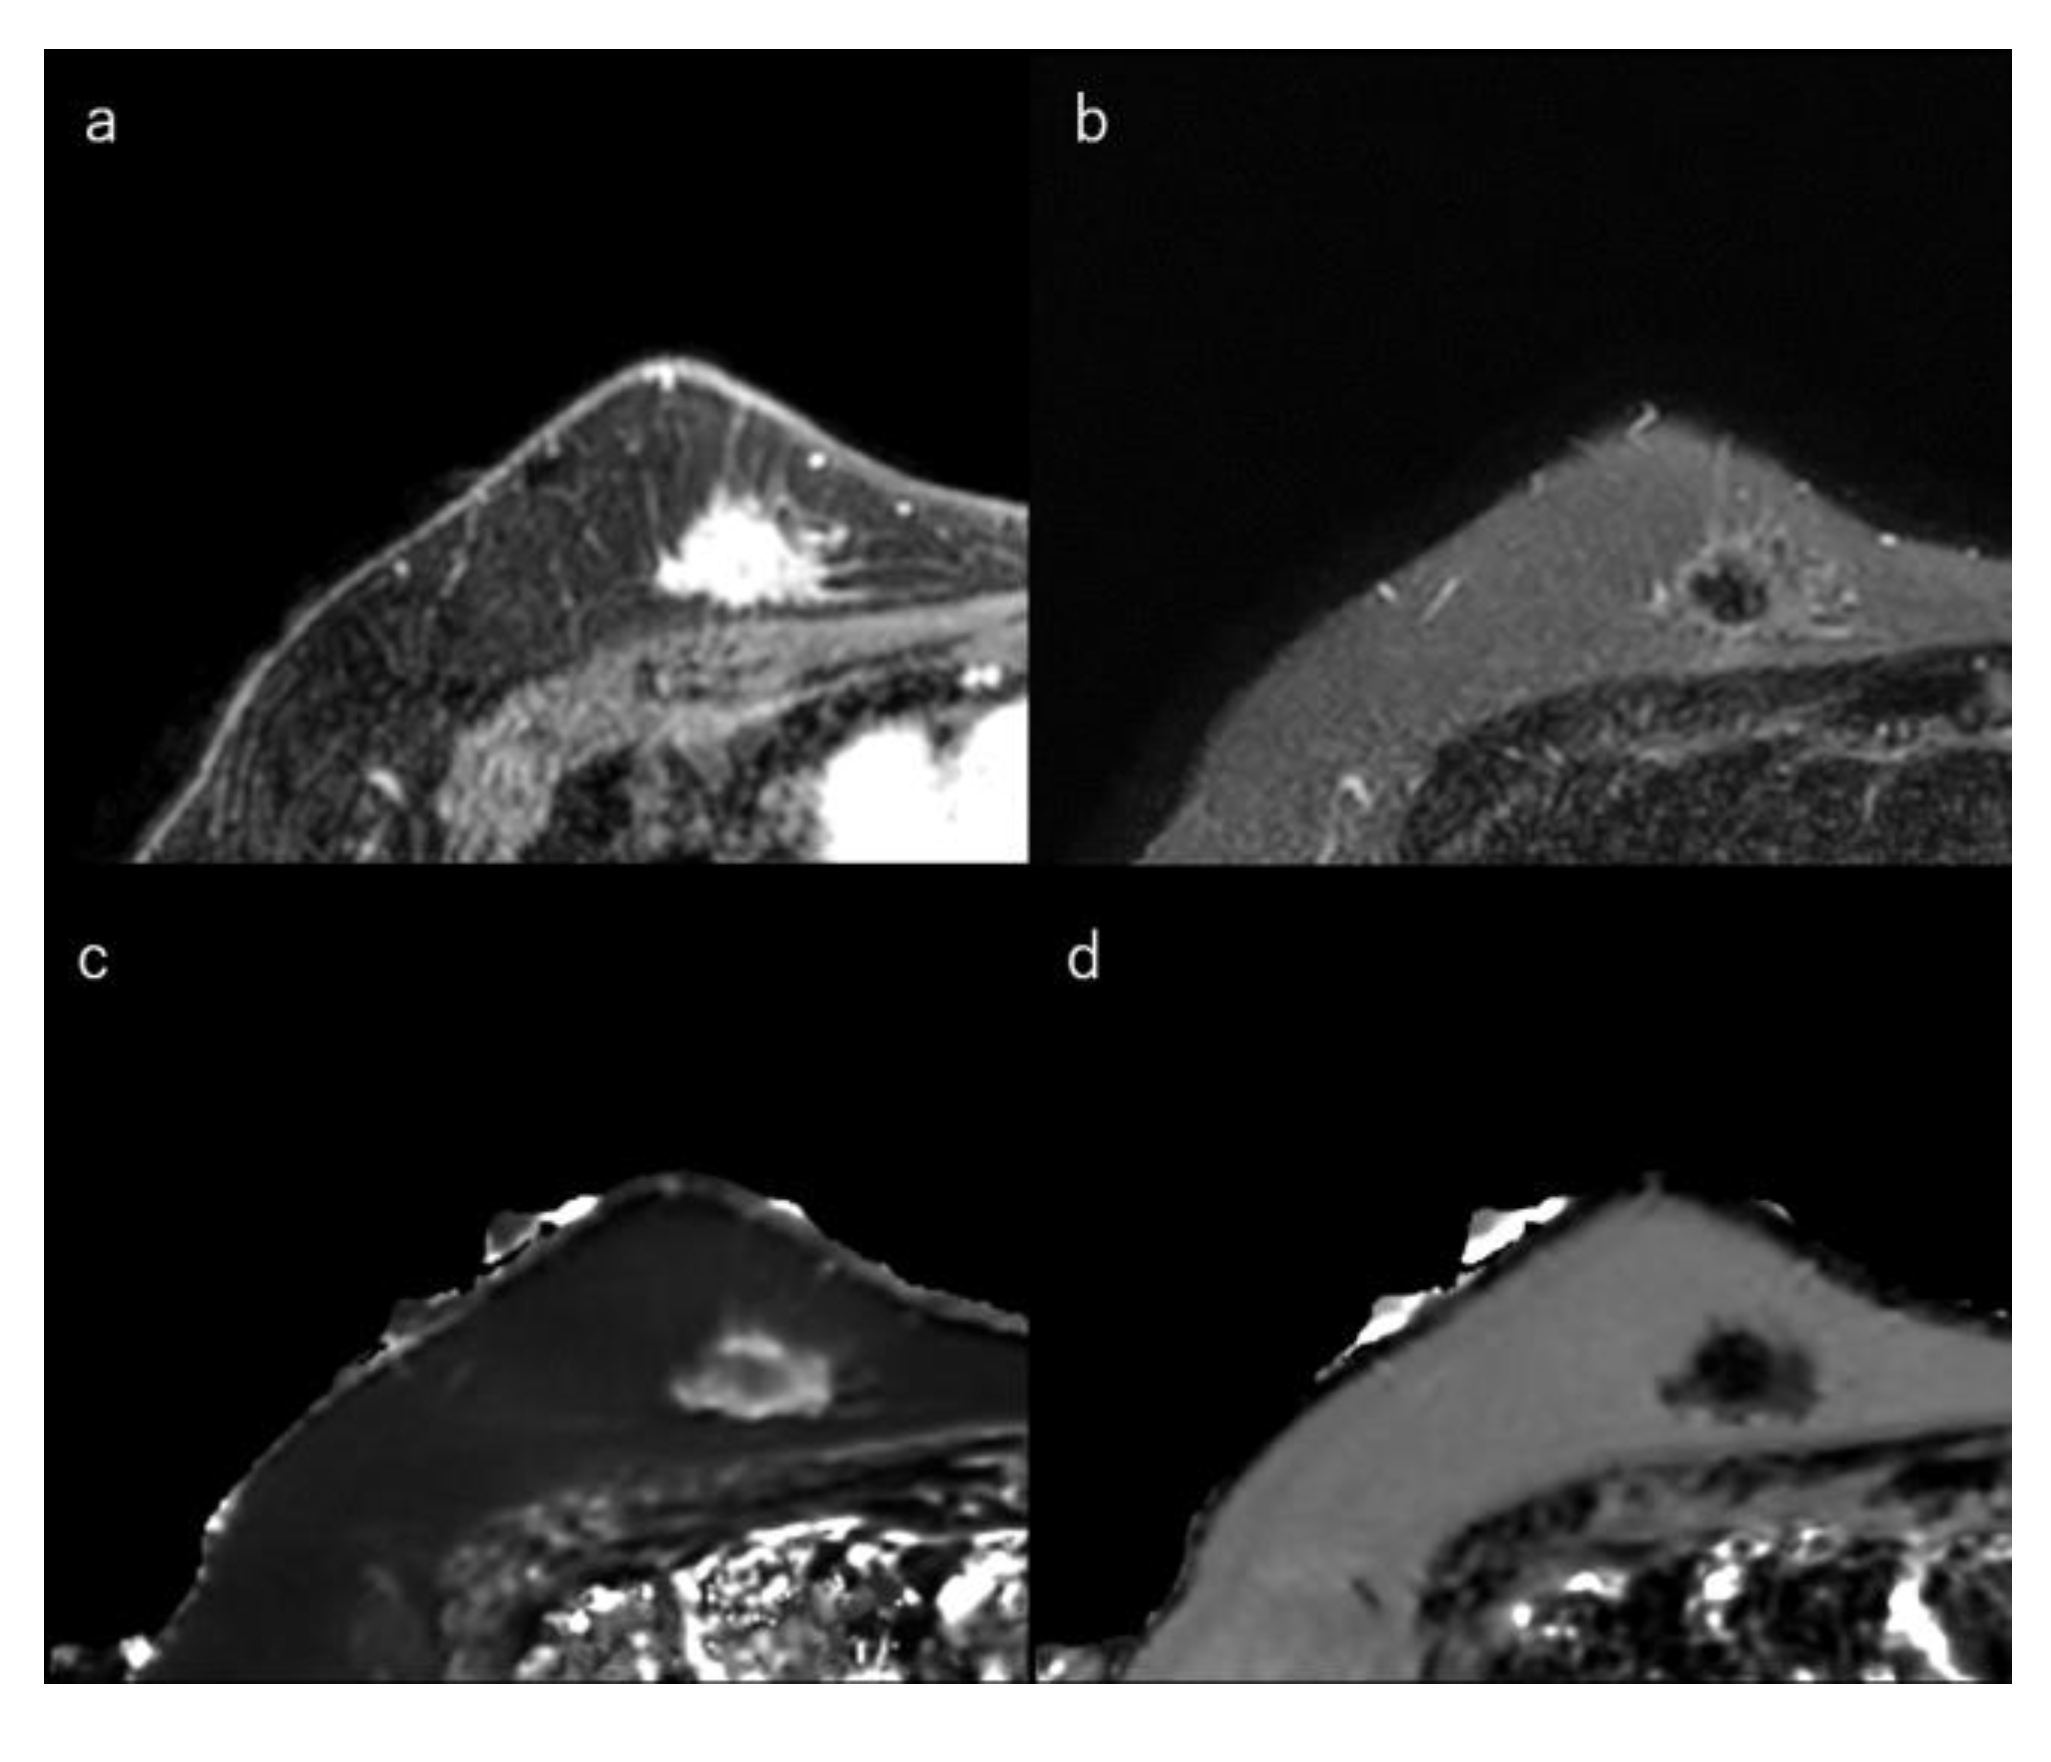

Figure 6.

(a) Dynamic contrast-enhanced MR image in a 73-year-old woman with triple-negative breast cancer shows an irregular mass with rim enhancement. (b) Short-tau inversion recovery image shows focal areas of very high signal within the mass. (c) T1 map (window width/centre = 1400/2400 ms) shows focal very high signals; Mean T1 of the mass is 1533 ms. (d) T2 map (window width/centre = 160/240 ms) shows focal very high signals within the mass; and mean T2 of the mass is 113 ms.

TN breast cancer is highly associated with the presence of a central scar, tumour necrosis, the presence of spindle cells or squamous metaplasia, high total mitotic count, and high nuclear-cytoplasmic ratio [9,10,145]. These cancers are also more likely to show round, oval, or lobulated masses and are more likely to be unifocal compared to ER+/PR+/HER2 tumours [29,145,146,161,162]. MRI often shows areas of intratumoral high T2 signal intensity, lobulated shape, rim enhancement, and smooth margins (Figure 6) [29,144,145,146,162]. The rim enhancement can be explained by high angiogenesis in the periphery of the tumour. Very high intratumoral signal intensity on T2-weighted MR images and an elongated T2 relaxation time may be associated with intratumoral necrosis [29,123,145]. When the necrotic areas are included, the ADCs of TN cancers are higher than of luminal-type breast cancers [29,51,78,96].